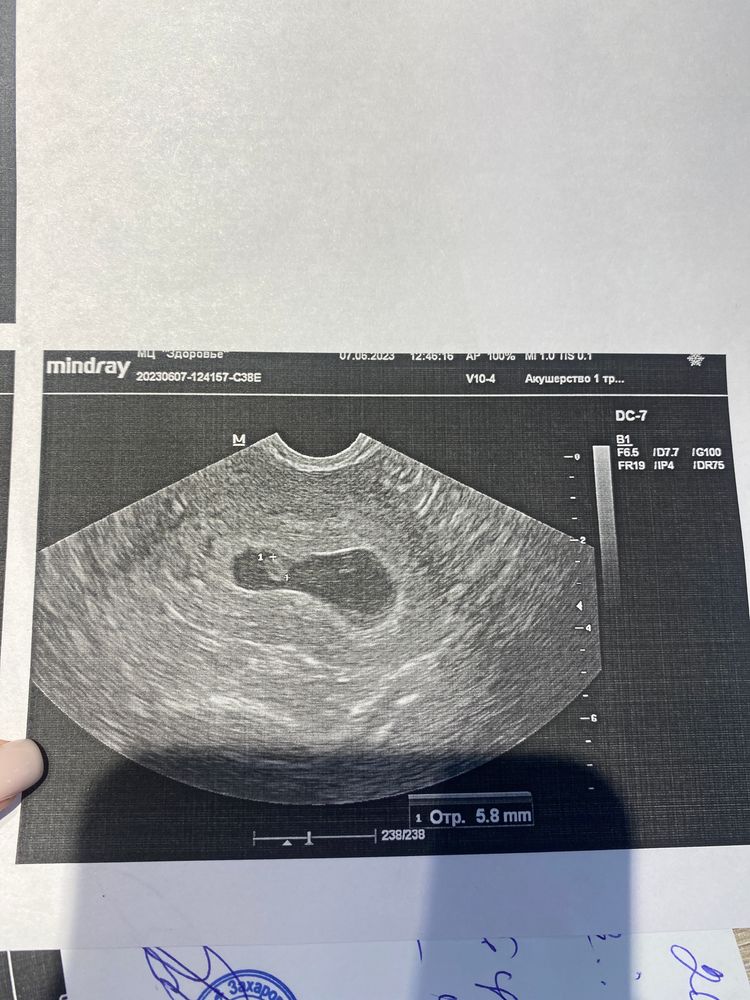

Лилия, даже не обратила внимание, что написала 1,7мм, потому что тоже голова не ,,варит,,. 17 мм. Через три дня опять пошла на УЗИ, уже хоть что то, но разглядели. Вообще цикл у меня 30-31, но в прошлый цикл была бхб, и месячные пошли на 37 день, может быть и этот цикл не был 30 дней и овуляция была поздняя, кто его знает...Но нервы конечно на пределе уже. Изображение